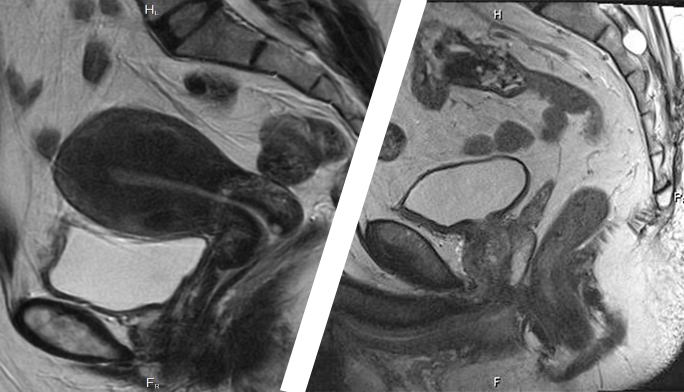

Որովայնի խոռոչի, փոքր կոնքի օրգանների մագնիսա-ռեզոնանսային տոմոգրաֆիան (ՄՌՏ) այսօր համարվում է ժամանակակից ախտորոշման ամենաօգտակար և անհրաժեշտ եղանակներից մեկը: Այն հարկ է իրականացնել փոքր կոնքի շրջանում ցանկացած բնույթի ցավի կամ անհարմարության առաջացման դեպքում, ինչը կօգնի խուսափել բարդություններից, կնպաստի արդյունավետ բուժմանը, ընդ որում, փոքր կոնքի ՄՌՏ-ի գինն այնքան մեծ չէ, որքան նրա իրականացումից ստացված օգուտը:

Փոքր կոնքի օրգանների ՄՌՏ-ն հնարավորություն է տալիս օրգաններում գոյացություններ հայտնաբերել դեռևս նրանց վաղ փուլում, ինչպես նաև կանխատեսել նրանց առաջացումը: Սովորաբար, կանանց մոտ

ՄՌՏ հետազոտության են ենթարկում հետևյալ օրգանները.

- միզապարկ,

- հեշտոց,

- արգանդ, հետարգանդային տարածություն:

Տղամարդկանց մոտ փոքր կոնքի ՄՌՏ իրականացվում է շագանակագեղձի, սերմնաբշտերի, ամորձապարկի հետ կապված խնդիրների ժամանակ:

Խնդրի հայտնաբերման նպատակով կատարվում է է սերմնատար ծորանների, շագանակագեղձի, հավելումների հետազոտություն: Արդյունքում ստացվում են բարձրորակ պատկերներ, որոնք օգնում են մասնագետին լիարժեք ախտորոշում իրականացնել: